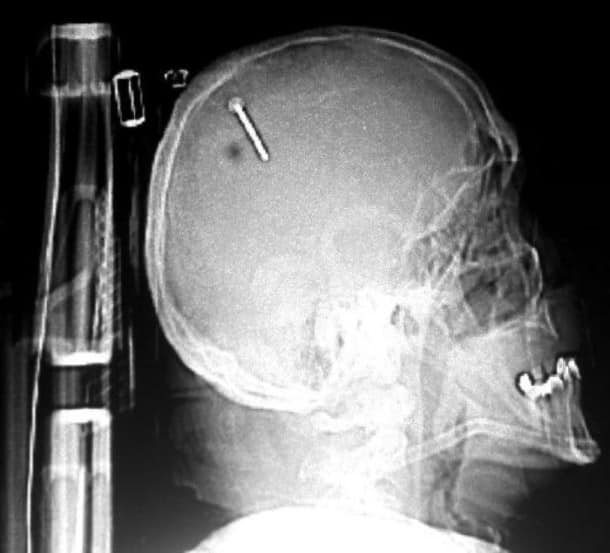

33 radiographies qui prouvent que les gens font des choses douteuses avec leur corps !